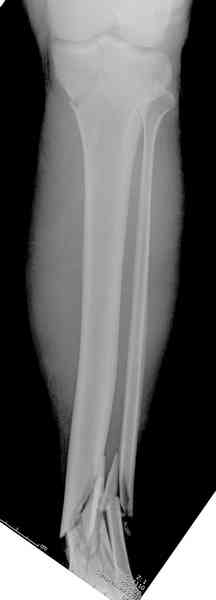

При высокоскоростных переломах редко можно встретить изолированную травму пилона, и в моей практике изолированные травмы большая редкость, поэтому, как дополнение к обсуждаемой теме, решил представить свежий, двухдневной давности случай.

Предыдущей сменой до 4:00 утра по поводу открытого перелома бедра, тибиал плато, пилон и надколенника сделана операция.

Пострадавшему 21 г., травма скоростная, после I&D с расширением раны, на бедре сделана операция ретроградным интрамедуллярным штифтом, остеосинтез с частичной резекцией надколенника и ушивание собственной связки.

Из всех внутрисуставных переломов дистального конца голени, Rüedi и Allgöver 2 и 3 представляют собой одну из самых больших проблем для ортопедов, занимающихся травмой. Эти повреждения, как правило, вызываются большой энергией и сопровождаются тяжёлой травмой мягких тканей.

Термин "ibial pilon" был предложен французским радиологом Destot в 1911, который сравнил взрывчатое воздействие таранной кости на суставную поверхность голени с молотком, ударяющим гвоздь. Первичное усилие, вертикально направленное через таранную кость на суставную поверхность большеберцовой кости, ведёт к перелому с различной степенью дробления суставной поверхности и прилегающего метафиза, порой доходящего до дистальной части диафиза, повреждению внутрисуставного хряща и мягких тканей.